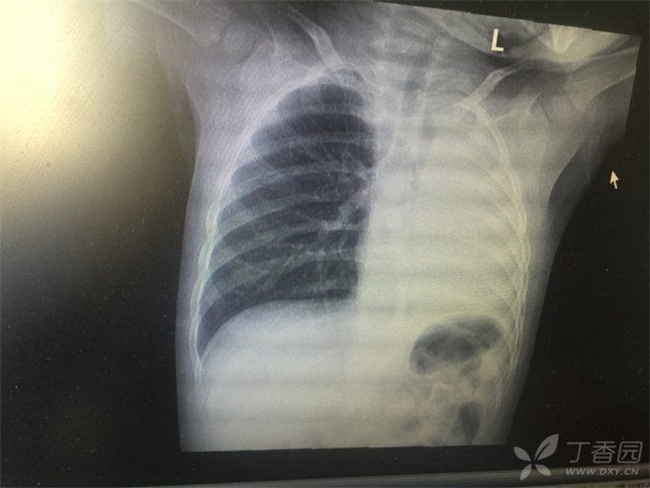

感染新冠会变“白肺”吗 新冠感染后可能变“白肺”吗

新冠感染后可能变“白肺”?感染新冠有可能会出现白肺,出现白肺意味着肺部出现了病变,因为病毒感染肺部而出现炎症反应比较严重,进行X光检查时肺部就会出现大片白色阴影,所以被称为白肺,并且伴随着呼吸急促、呼吸